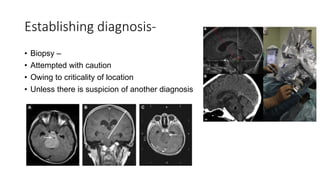

Establishing diagnosis-

• Biopsy –

• Attempted with caution

• Owing to criticality of location

• Unless there is suspicion of another diagnosis